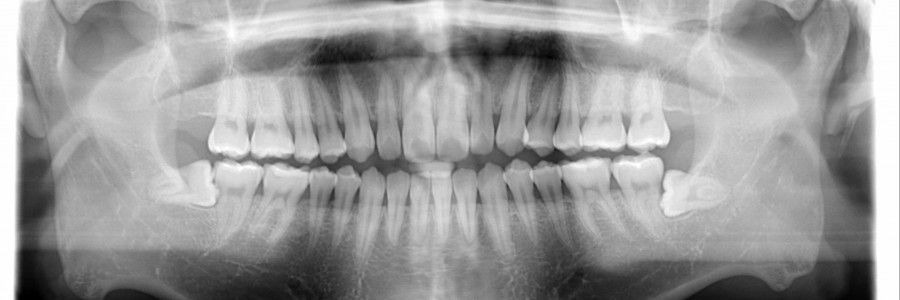

A. 사랑니는 좁고, 충분치 않은 공간에서 나기 때문에 대부분 제대로 나지 못하는 경우가 많아 통증을 동반합니다 어금니쪽으로 기울어져서 나거나 수평으로 자라게 되면 주변 치아나 신경을 건드리게 되어 통증을 느끼게 됩니다. 그 외 치아가 고르지 못하게 되면 음식물이 사랑니 뒤쪽에 끼게되어 칫솔질로 제거 되지 못해 치주질환등을 유발시키기 때문에 발치하는게 좋습니다.

A. 턱이 잘 발달되어 있어 주변치아와 턱뼈에 영향을 주지 않고, 정상적으로 맹출되는 경우 외에는 빼주는것이 좋습니다. 당장에 큰 이상이 없다 해서 그냥 두었을 경우 나중에 더 큰 비용이나 어려움이 초래될수 있습니다